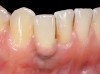

Problem: The implant is placed too facially, and there is significant labial gingival recession, contour change, and mucosal discoloration around the implant, abutment, and crown (Figure 3 and Figure 4). The implant attachment apparatus is intact and healthy, but the patient has a thin periodontal phenotype.

The following case report provides an example of this case scenario: A 28-year-old white female patient presented with her maxillary right lateral incisor significantly longer than the contralateral tooth following restoration of an existing crown that was 10 years old (Figure 3). The patient was dissatisfied with the esthetic appearance of the restoration due to the increased length, recession of the gingival tissues, and discoloration of the surrounding mucosa (Figure 4). Similar to case scenario No. 1, the first step in treatment was to decoronate the healthy implant by placing a flat surgical cover screw and employing a provisional resin-bonded-retained (RBR) prosthesis as a transitional fixed restoration (Figure 5 and Figure 6). The gingival augmentation in situ was allowed to take place for 2 to 3 weeks and was evaluated after that time (Figure 7).

Fig 3. A patient presented with a high smile line and midfacial recession of the maxillary right lateral incisor as evidenced by the increased tooth length compared with the contralateral lateral incisor.

Fig 4. Intraoral view of tooth No. 7 with the gingival zenith more apical than the adjacent central incisor and canine tooth.